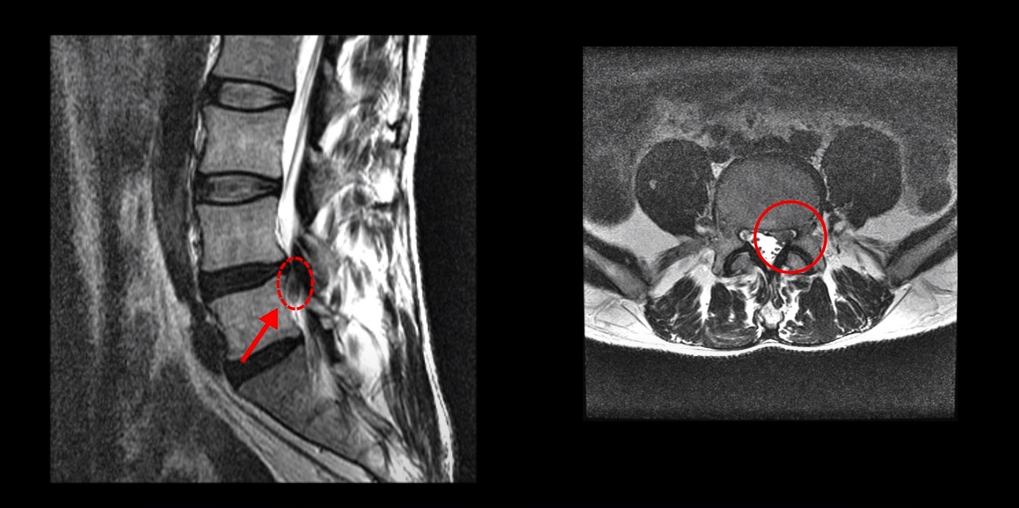

이 환자분에 대해 더 자세히 설명 드리겠습니다. 이분은 약 40일 전 농장에서 풀 뽑기를 한 후 허리디스크가 심하게 파열되어 극심한 방사통과 감각 마비가 생깁니다. 이분 MRI를 보면 4번 5번 마디가 심하게 파열되어 수핵이 아래로 많이 흘러내려 있습니다.

수핵이 왼쪽으로 밀려나와 있어서 극심한 왼쪽 다리 방사통과 감각 마비가 있습니다.